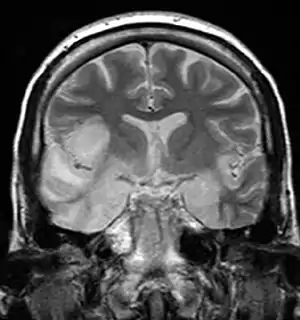

![]() Imaginea scanată IRM arată un semnal ridicat în lobii temporali și girusul frontal inferior drept la cineva cu encefalită HSV. | |